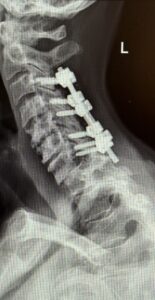

The patient underwent a one-day, two-stage procedure. Stage 1 was a C6-7, C7-T1 anterior cervical discectomy and fusion with reduction of the anterolisthesis and correction of the kyphosis.

Stage 1 was immediately followed by Stage 2 which was extension of her posterior instrumentation and fusion from C3 down to T3. Neuro-navigation was used to assist with the difficult anatomy of the upper thoracic spine.